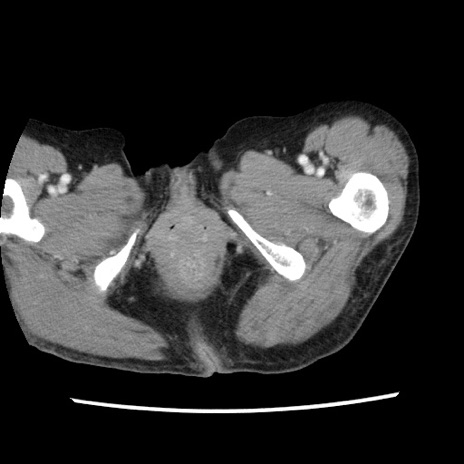

症例1(横断像)

【症例】80歳代女性

【主訴】腹痛

【現病歴】8時間前から腹痛あり来院。

【既往歴】糖尿病、脂質異常症、子宮体癌にて子宮全摘術

【身体所見】意識清明・会話良好だが腹痛で苦悶様、全腹部にわたって反跳痛と圧痛あり

【データ】WBC 13600、CRP 0.14、LDH 224、CK 90